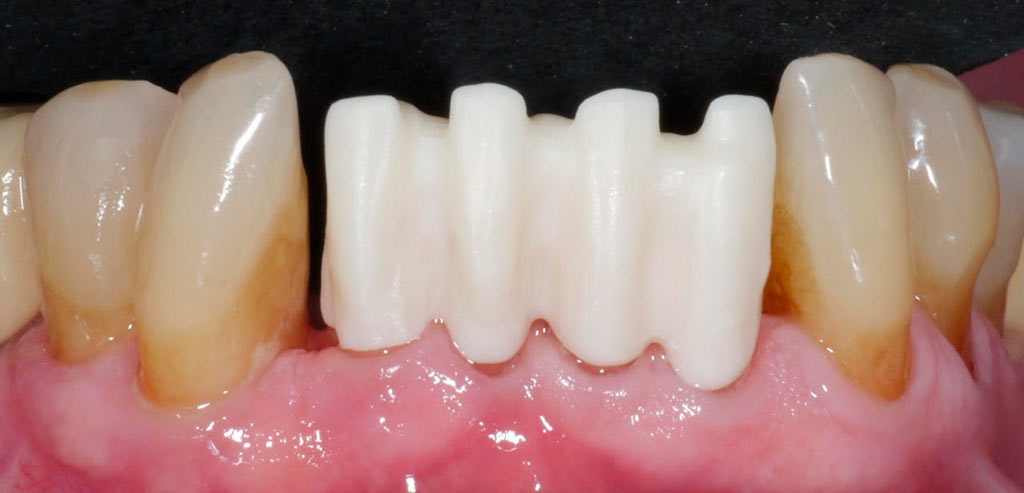

Rehabilitacion de paciente con destrucción dental